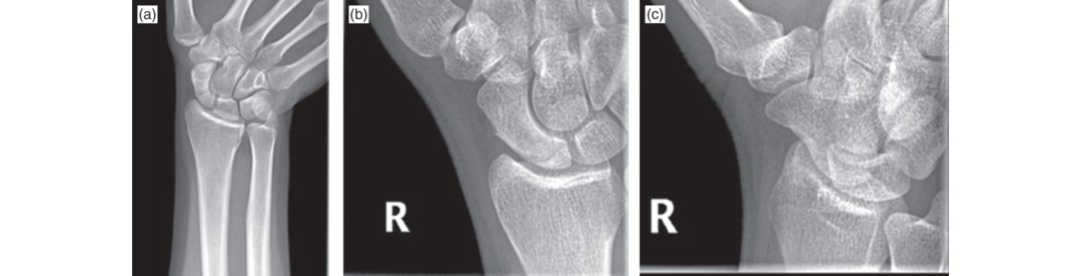

This article provides essential research regarding The Growing Problem of Osteoporosis: Your Guide to Prevention & Treatment. Osteoporosis is a condition weakening bones and causing brittle fractures, impacting quality of life with pain, disability, and even death. The problem of osteoporosis is escalating, driven by an aging population, lifestyle changes, and improved diagnosis. Addressing this serious health concern is crucial for improving public health and well-being across all ages.